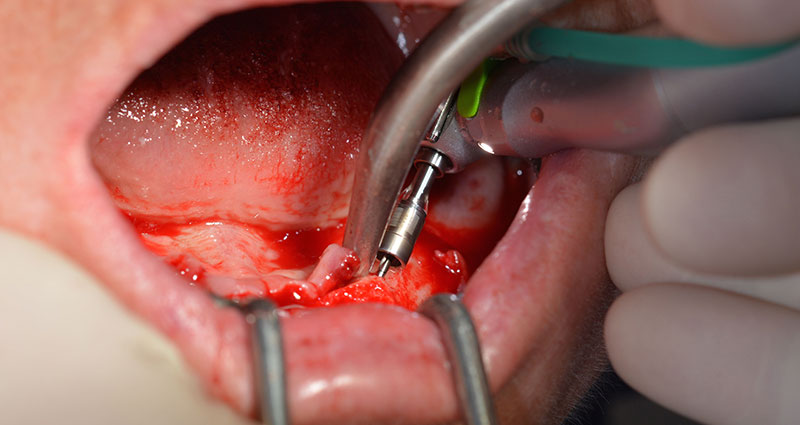

Hierbei zeigen sich die ersten Vorteile von Implantmed. Das chirurgische Protokoll ist bereits voreingestellt und an festen Positionen gespeichert. Die einzelnen Positionen sind sowohl über einen einfachen Druck auf die Position „P“ der Fußsteuerung anwählbar, als auch auf dem Display selbst. Die in diesem Fall an Position 1 voreingestellte Umdrehungszahl von 35.000/min wird auf dem beleuchteten Display ebenfalls groß angezeigt (Abb. 5 und 6).

Das chirurgische Protokoll der verwendeten Implantate (SKY, bredent medical) schreibt eine Umdrehungszahl von 1.200/min für die Pilotbohrungen vor (Abb. 7–9).